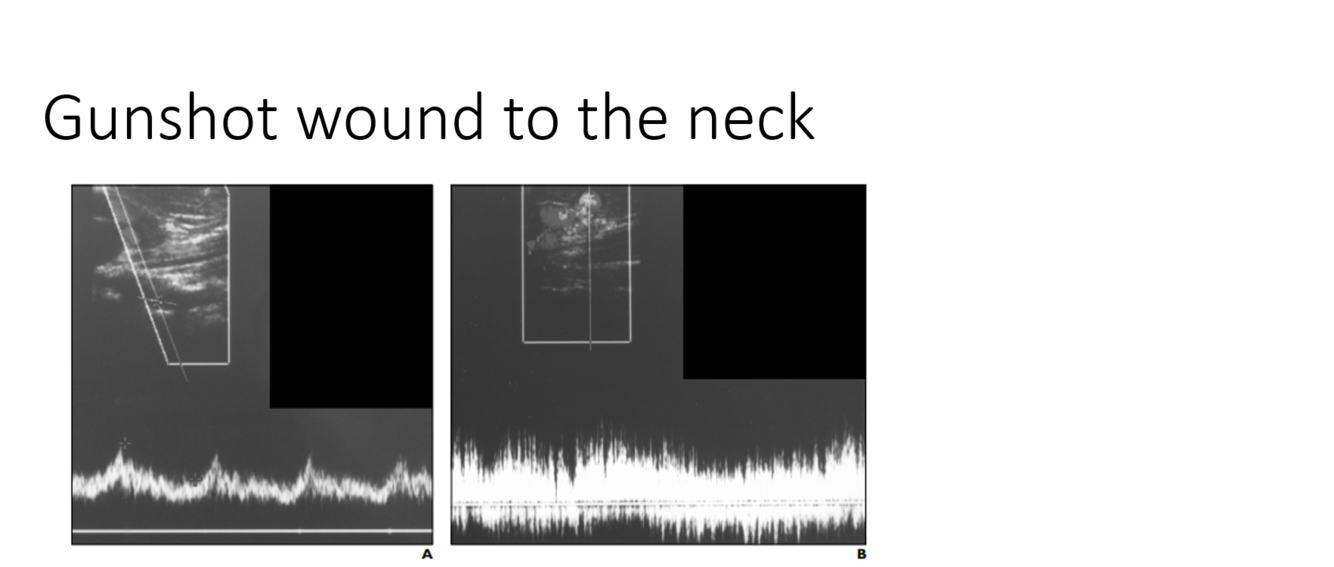

if you are given a doppler US of the vertebral artery. most likely diagnosis?

subclavian steal.